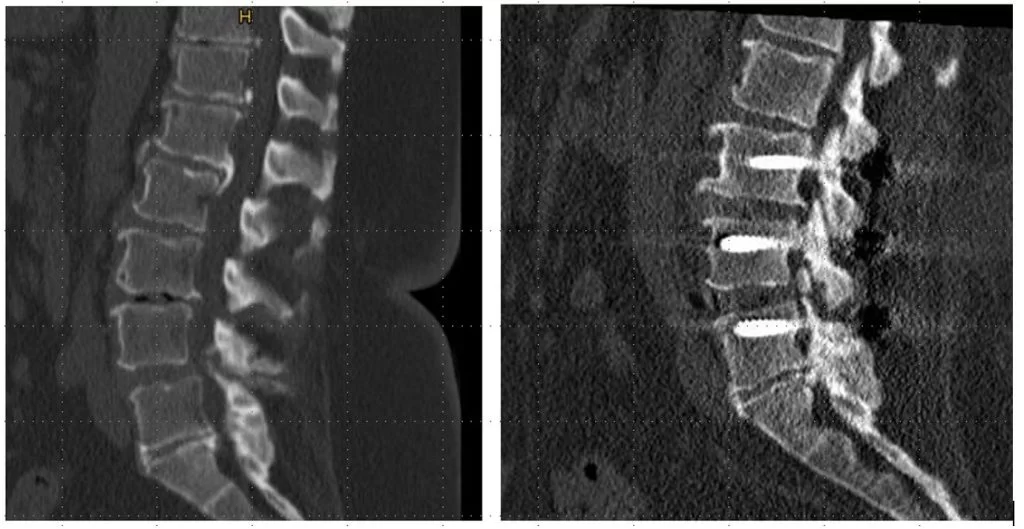

- Αστάθεια σπονδυλικής στήλης: Η σπονδυλική στήλη μπορεί να γίνει ασταθής εάν υπάρχει μη φυσιολογική ή υπερβολική κίνηση μεταξύ δύο σπονδύλων. Αυτή είναι μια κοινή επιπλοκή πχ.της σοβαρής αρθρίτιδας στη σπονδυλική στήλη. Η σπονδυλοδεσία μπορεί να χρησιμοποιηθεί για την αποκατάσταση της σταθερότητας της σπονδυλικής στήλης σε τέτοιες περιπτώσεις (Εικόνα 1 και 2).

Η προσπέλαση μπορεί να είναι πρόσθια (δηλαδή από μπροστά, όπως πχ. συχνά στον αυχένα, Εικόνα 2), οπίσθια (όπως πχ. συχνά στη μέση, Εικόνα 3) ή και πλάγια (όπως πχ. σε τεχνικές όπως το XLIF κλπ.)